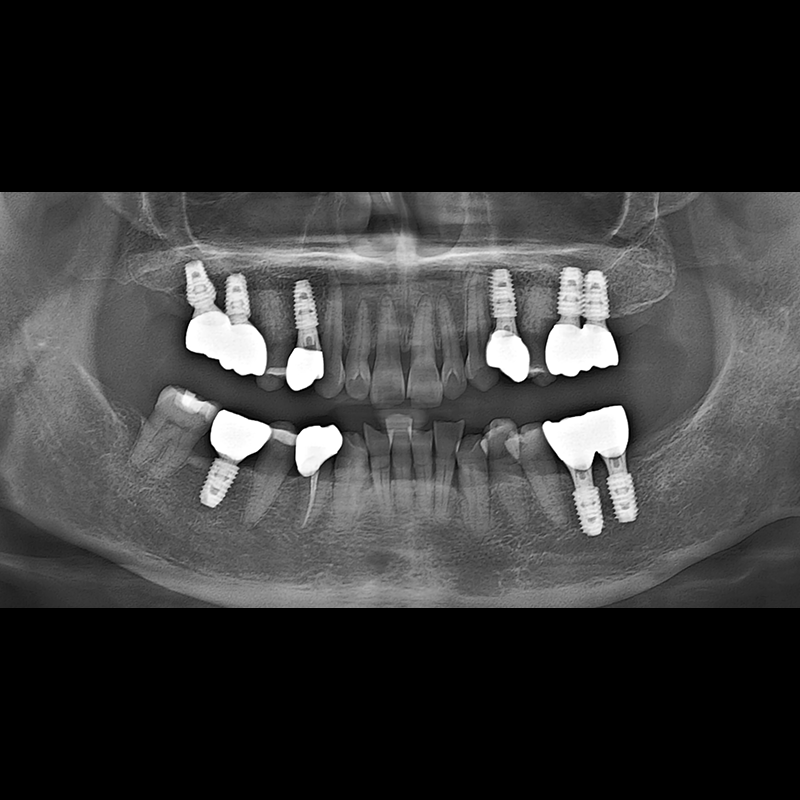

BEFORE AFTER

种植牙前后的照片 2025.05.30

在缺失的牙齿部分和难以挽救的牙齿位置植入了种植牙。